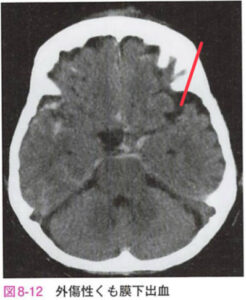

| 外傷性SAH | 脳底槽のくも膜下出血はびまん性脳損傷の間接的初見とも言われている。脳血管攣縮を合併することもある。![]() |

|